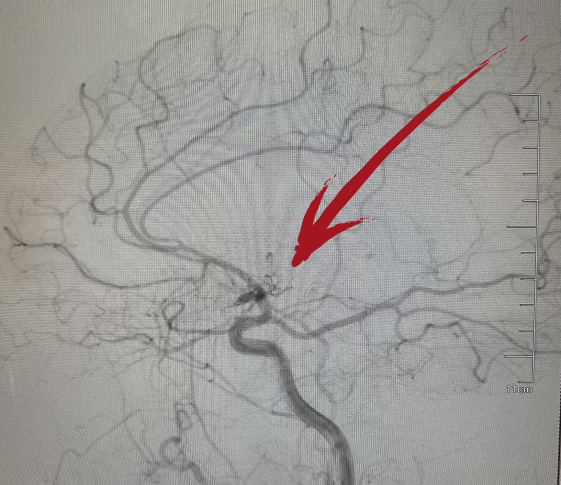

▲术后DSA提示右侧大脑中动脉已开通

从患者到院到穿刺成功仅耗时50分钟,到血管开通耗时100分钟,术后,患者肢体瘫痪及言语不利明显好转。

经过一周的住院治疗,患者肢体活动及言语功能基本恢复正常,顺利出院。